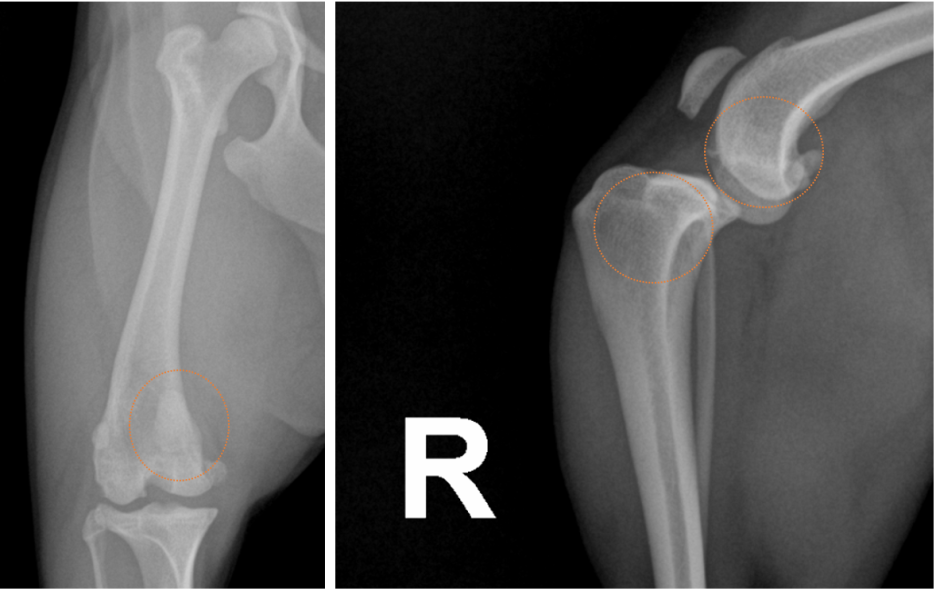

해당 강아지 환자는 보행체크 후, X-Ray(방사선) 촬영을 진행하였습니다.

방사선 사진 상 안쪽으로 빠져 있는 슬개골과 무릎 관절 사이에 신생된 뼈 조직, 정상보다 전방으로 튀어나온 종아리뼈가 확인됩니다

최종적으로 오른쪽 뒷 다리 슬개골탈구 3기 + 십자인대 파열 + 퇴행성 관절염 이 같이 진단되었으며, 보호자님과 상의하에 수술이 결정되었습니다.

울산 강아지 슬개골 십자인대 엑스레이 / 출처: 에스동물메디컬센터